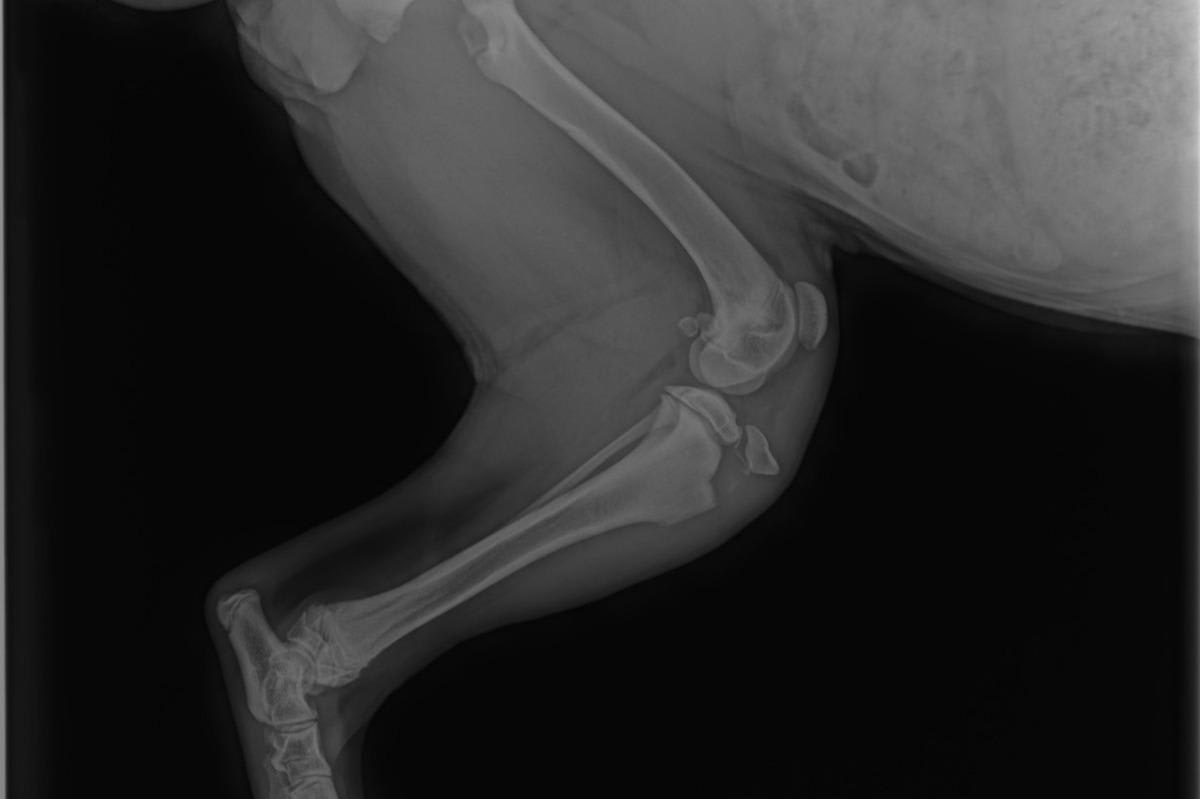

I have a 5 month old Bernese Mountain Dog, the photo is a x-ray of her leg, we are being told it will cost $3000 to fix the fracture. Will this heal on its own and are they are taking us on a run for our money? Or does this really need a $3000 surgery?

I am so sorry to hear about your puppy! Unfortunately it appears she has a tibial crest avulsion, and the treatment of choice is surgery if you want to have Bailey have the ability to use her leg normally. Unfortunately orthopedic surgeries do cost a great deal of money to perform and so vets have to charge accordingly. You can always see if there is a veterinary school in your area that may offer the surgery at a lower cost, but that isn't always a gaurantee.